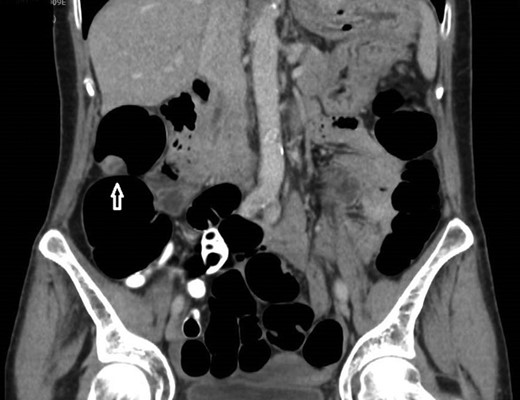

12 mm polypoidal mass (white arrow) visible on coronal image of post-contrast CTVC.

In view of this CT Colonoscopy was performed, alongside a CT Chest examination. This showed a 12 mm lesion arising from the lateral wall of the ascending colon. It appeared rounded and mural-based, and displayed irregular peripheral enhancement post-contrast. It did not conform with a lipomatous lesion, with an average internal density of approximately 40 HU. No other colonic lesions were demonstrated, and no locoregional adenopathy or distant metastases were identified.